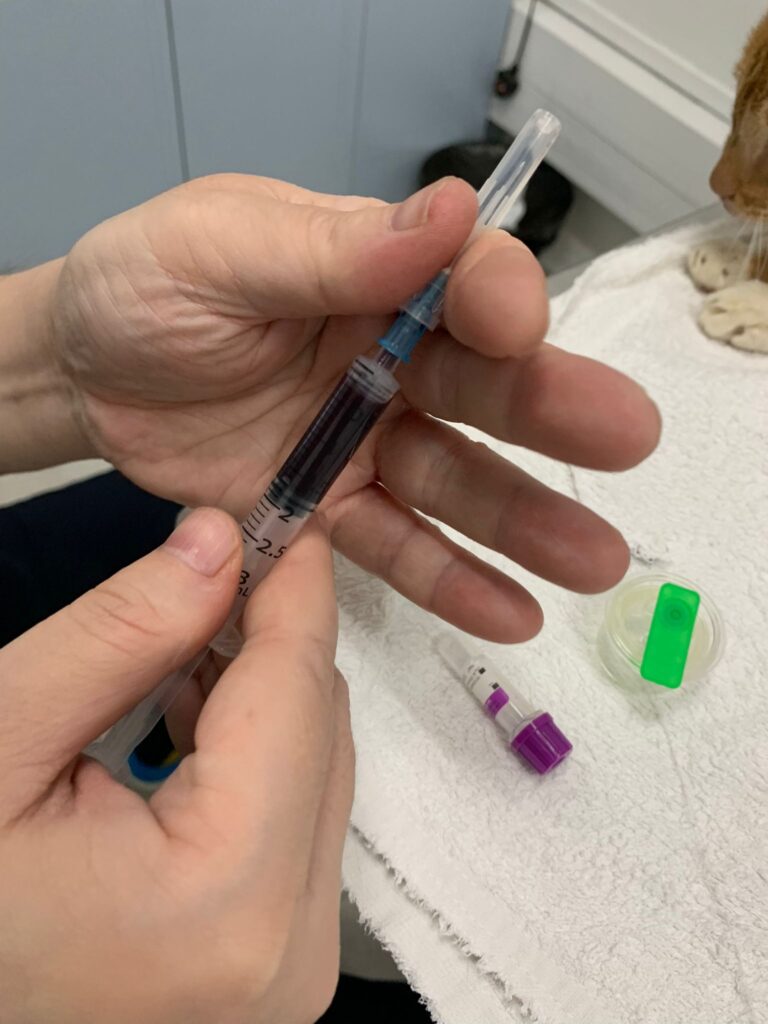

To take Cbc. Blood taken from his left jacular – easy and steady.